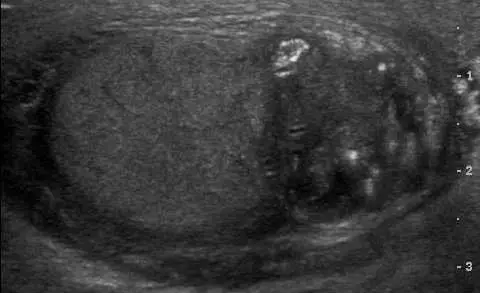

本張陰囊超音波影像(灰階,B-mode)顯示:

- 左側(較大的橢圓形結構):睪丸(testis),回音均勻,輪廓完整,回音質地相對正常

- 右側(鄰近睪丸的不均質結構):副睪(epididymis),呈現明顯腫大,內部回音不均質(heterogeneous),可見多個強回音點及結節狀改變

- 副睪頭部(epididymal head)尤其明顯腫大,與正常睪丸相比有顯著對比

- 無明顯游離積液(陰囊積水)的無回音層包繞

- 影像右側標示有 -1、-2、-3 刻度,為測量副睪厚度的游標標記

此影像的副睪腫大、回音不均質,結合陰囊痛 1 週的臨床情境,符合**副睪炎(epididymitis)**的典型超音波表現。